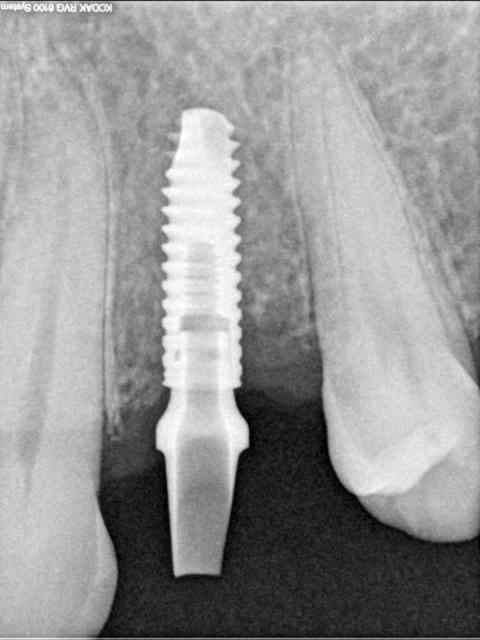

3f3boxni50k58rq7e9ce9ddqrxgk - Eugenol

dentiste57

11/06/2011 à 01h31

oups!! j'ai merdouillé dans les photos, je corrige.

aujourd'hui donc...

je revois le patient, l'implant est bel est bien supra crestal et la prothèse va donc être impossible à gérer.

d'autant plus que les piliers sont des piliers platform switching ce qui va rendre ceux ci complètement visibles.

bref, je prends la décision de soit explanter soit implanter plus profond.

c'est la deuxième solution que je retiens car l'os du patient était extrêmement mou ( type 4).

j'ai même pas eu d'efforts à faire pour pousser(visser) l'implant un peu plus loin!!!

bon j'ai oublié de faire une photo post op, mais je suis sure que vous me pardonnerez, c'est le week end après tout non ?